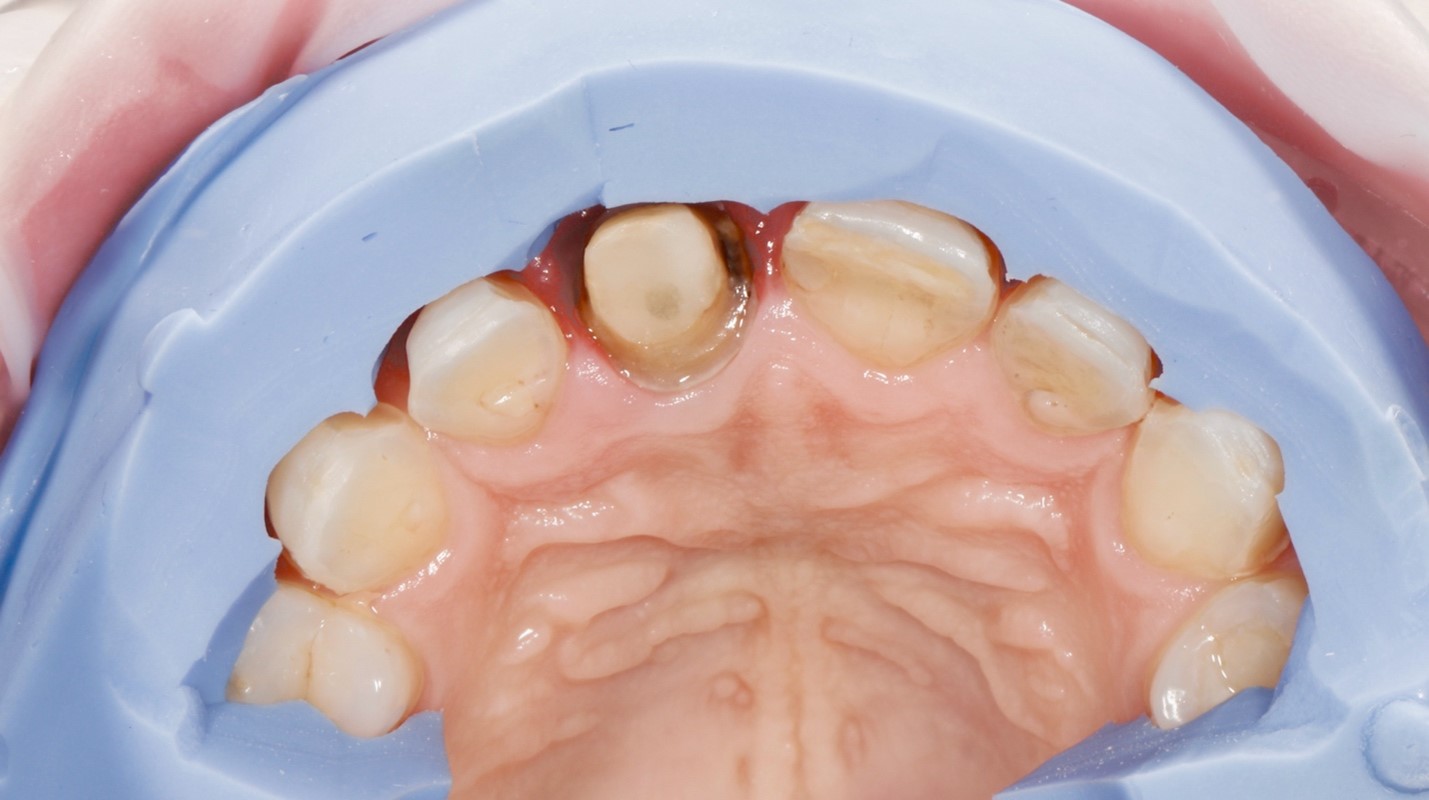

Пациентка И., 43 лет, обратилась в клинику с жалобами на эстетику передних зубов (рис. 1). Зуб 21 ранее проходил эндодонтическое лечение более шести лет назад. На момент первичного осмотра зуб был восстановлен временной композитной коронкой. Зуб 11 имел более тёмный оттенок по сравнению с верхними боковыми резцами. После обсуждения плана лечения пациентка выбрала восстановление зубов с 13 по 23 с использованием керамических реставраций.

Рис. 1. A – вид передней группы зубов с ретракторами. Зуб 21 ранее был пролечен эндодонтически и восстановлен временной коронкой.